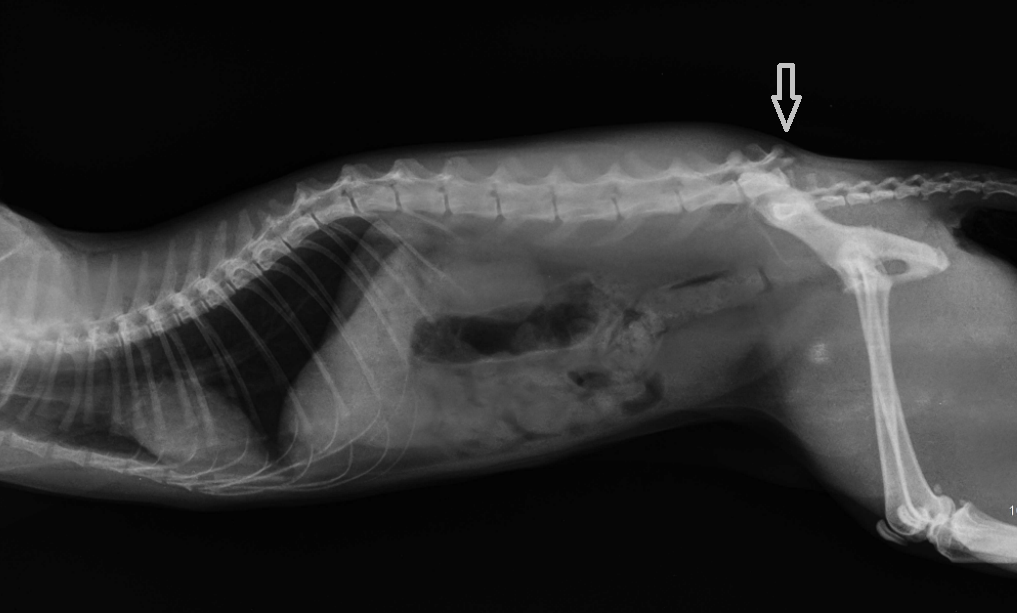

Рентгеновские снимки перелома лапы у кота: диагностика и лечение